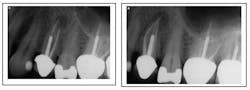

Missed MB2 canal